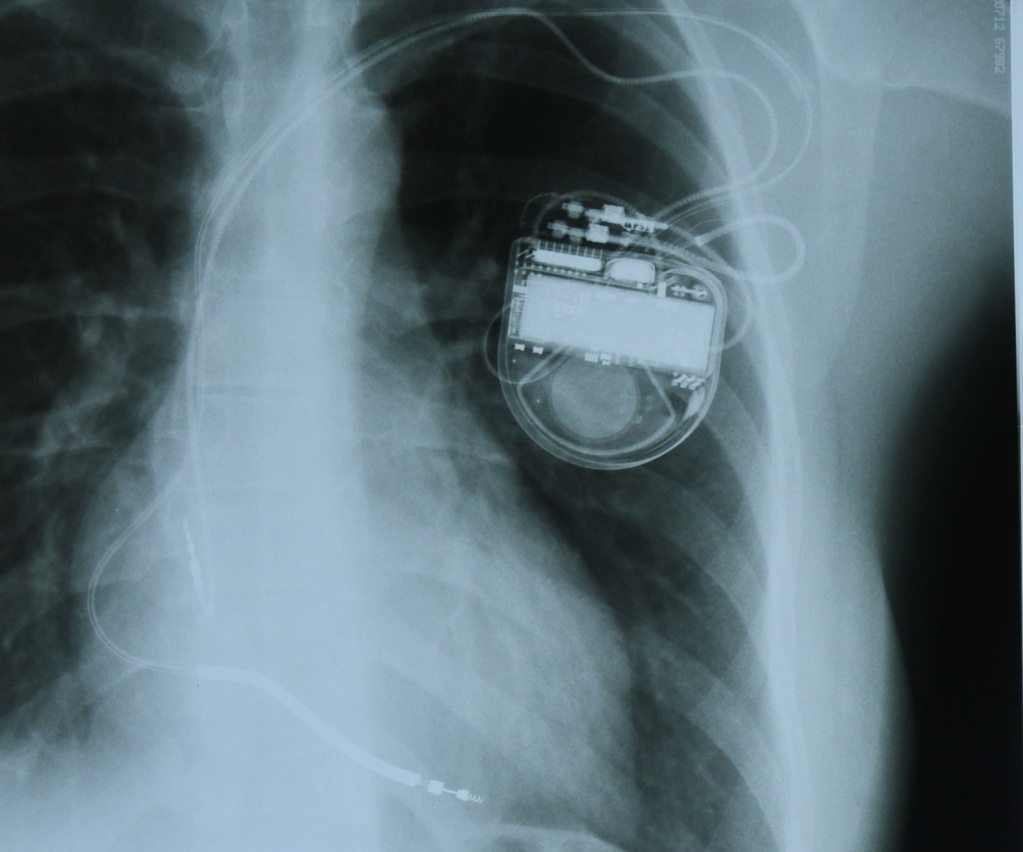

Устройство представляет собой небольшой, с ладошку, аппарат, состоящий из микросхемы и литиевой батарейки, который вшивают под большую грудную мышцу. Аппарат осуществляет считывание сердечных сокращений с помощью электродов, введенных в полость правого предсердия или правого желудочка, в зависимости от типа аритмии. То есть такая схема слежения за ритмом подобна обычной кардиограмме, но результаты этой записи фиксируются в микросхеме аппарата. В том случае, если ритм хороший, никакой электростимуляции не требуется. Если же у пациента произошел опасный для жизни приступ сердцебиения, кардиовертер улавливает эти нарушения и по электродам посылает сигнал небольшой мощности с целью синхронной деполяризации всех электрически активных клеток миокарда. Происходит электрическая «перезагрузка» миокарда, после чего должен восстановиться правильный ритм. Без кардиовертера сбой сердечного ритма может закончиться печально.

Операция проводится под местной анастезией. В подключичную вену вводится электрод кардиовертера. Под рентген-контролем его подводят к полости правого предсердия, а затем и в полость правого желудочка, «ввинчивают» электроды в их внутреннюю оболочку. А под кожу или под большую грудную мышцу подшивается сам аппарат. Когда рана затянется, а это произойдет на десятый день, он будет почти незаметен под кожей. Вся операция занимает не более часа и считается безболезненной для пациента. А на третий-четвертый день можно ехать домой и продолжать жить так, как хочется, не боясь проявлять самые разные эмоции. Ведь жизнь без эмоций, как небо без солнца, - неяркая и неинтересная.